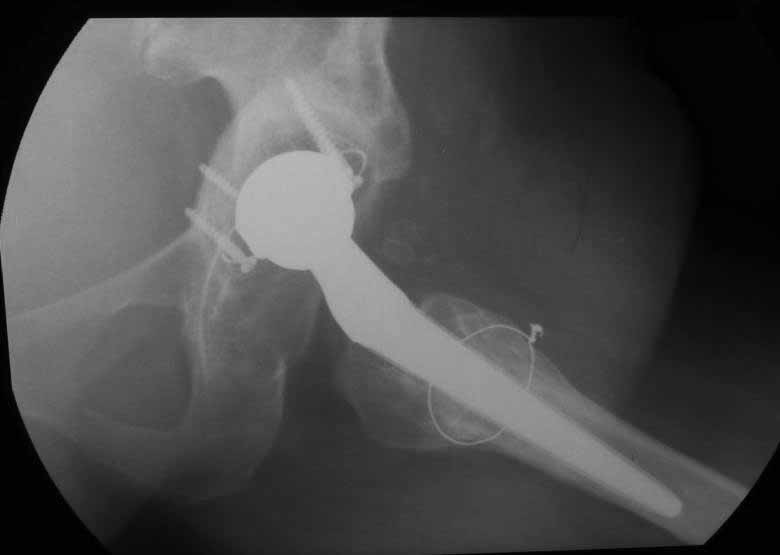

Уважаемые коллеги. Хотелось бы услышать мнения и советы по представляемому случаю.

Пациентка 45 лет. Бесцементное эндопротезирование левого тазобедренного сустава 6 лет

назад (впадина RM, Mathys, металл-металл, ножка Зульцеровская). За 10 лет до

протезирования коррегирующая остеотомия бедренной кости, которая не срослась в течение

года до удаления пластины, а затем срослась в течение 3 месяцев иммобилизации в кокситной

повязке. После протезирования получилось наблюдать пациентку почти постоянно, поскольку

через 2 года синтезировал ей лодыжки на оперированной стороне, затем, через несколько

месяцев удалил фиксаторы, а в 2009г. резецировал мениск на противоположной стороне. Боли

все эти годы не беспокоили. Пациентка чуть выше среднего роста, вес тела нормальный.

Физические нагрузки переносила хорошо. Работает на 7 этаже без лифта. Год назад экстирпация

матки по поводу лейомиомы больших размеров. Несколько месяцев назад появились боли в

области левого тазобедренного сустава. При рентгеновском и КТ исследованиях (июль с.г.)

нестабильность тазового компонента. От предложенной замены протеза пациентка на тот

момент, слава богу, отказалась. Через какое то время боли в области левого тазобедренного

сустава практически полностью прошли, а около 2 месяцев назад появилось ощущение

патологической подвижности таза и боли в паху справа, которые через некоторое время

уменьшились, а потом снова усилились после значительных физических нагрузок (много ходила

по песку на пляже, носила тяжести). Ежедневно принимала диклофенак. На рентгенограммах

переломы правой лонной кости. Сейчас госпитализирована из-за болей в паху справа. Боли

слева не беспокоят. На фоне снижения нагрузок в стационаре боли значимо уменьшились.

-Если думать о ревизии, то когда? На представленных снимках тазобедренный сустав до и

сразу после операции, затем 2 снимка 2009г., когда ничего не беспокоило, затем КТ 2-х

месячной давности и вчерашние рентгенограммы обоих тазобедренных суставов.